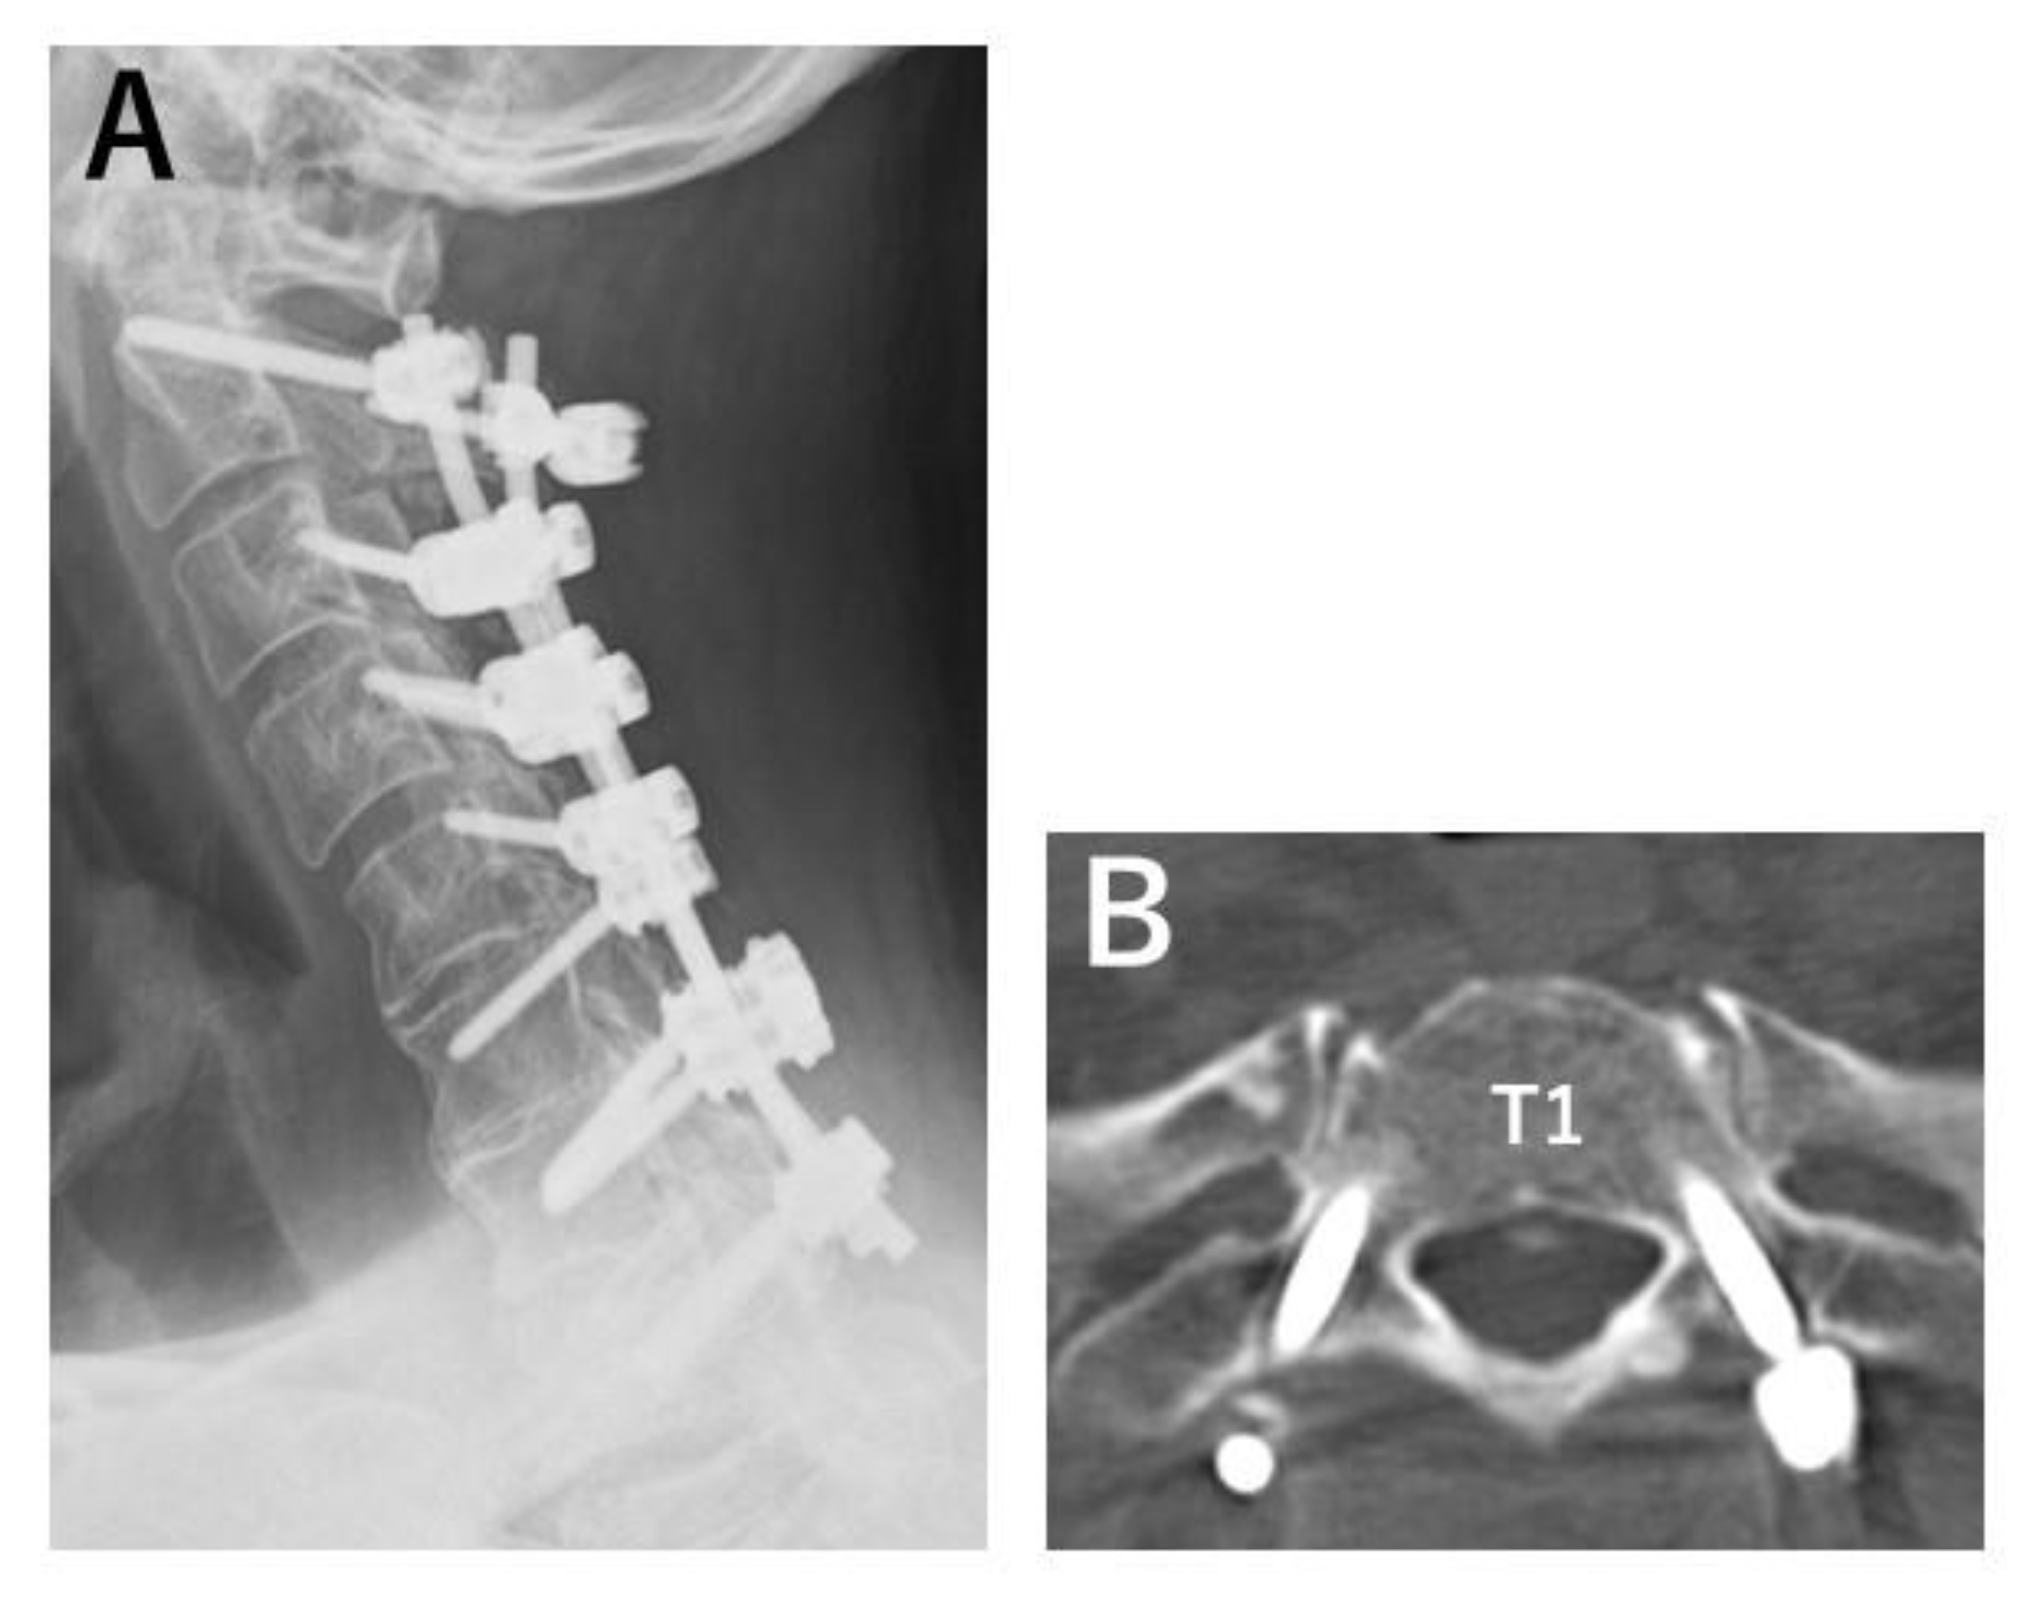

- Nagashima, K.; Koda, M.; Abe, T.; Kumagai, H.; Miura, K.; Fujii, K.; Noguchi, H.; Funayama, T.; Miyamoto, T.; Mannoji, C.; et al. Implant failure of pedicle screws in long-segment posterior cervical fusion is likely to occur at C7 and is avoidable by concomitant C6 or T1 buttress pedicle screws. J. Clin. Neurosci. 2019, 63, 106–109. [Google Scholar] [CrossRef]